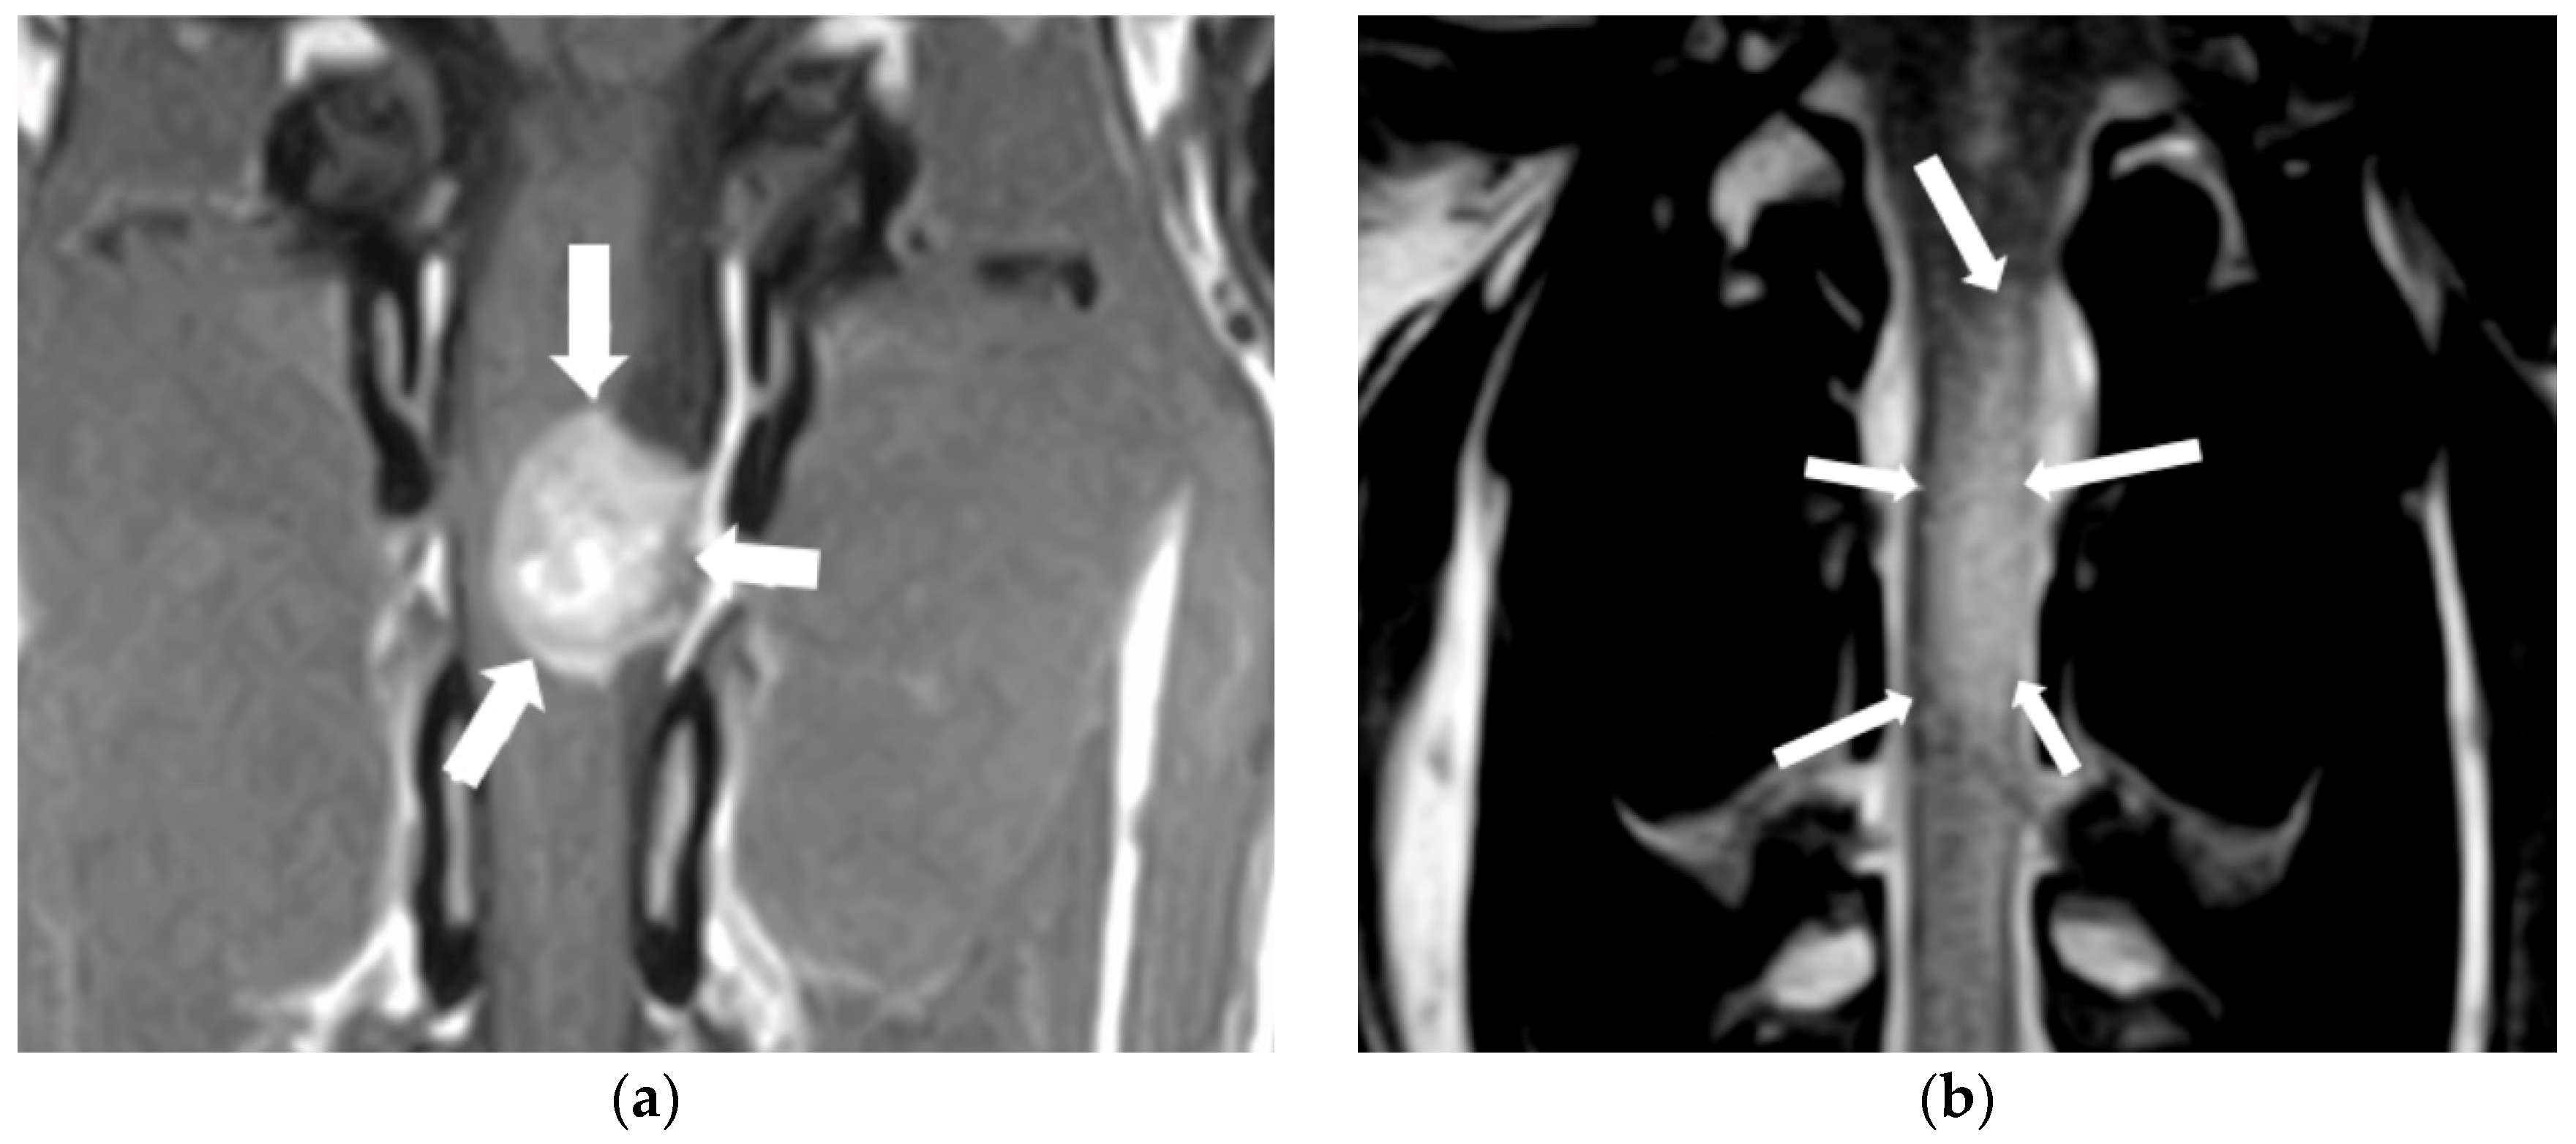

3.1. Intervertebral Disc Disease

3.3. Spinal Cord Neoplasia